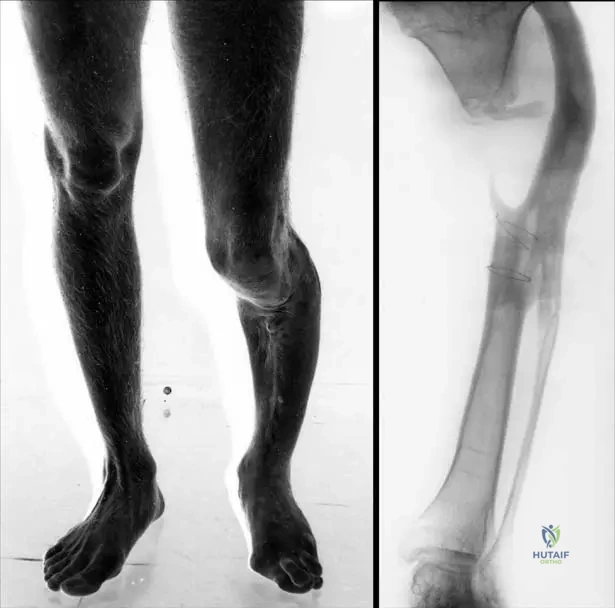

A 12-year-old male presents for evaluation of knee pain following a minor fall. Radiographs of the knee are obtained, revealing an incidental, sharply marginated, eccentric, metaphyseal lesion in the distal femur. He denies any prior symptoms related to this area. Physical examination is unremarkable. What is the most likely diagnosis?

View Answer & Explanation

Correct Answer: C

Rationale: Nonossifying fibromas (metaphyseal fibrous defects) are commonly detected incidentally in the second decade, are eccentric and metaphyseal, often in the distal femur, and are sharply marginated. The patient's age, incidental finding, and radiographic characteristics are classic for a nonossifying fibroma. Osteosarcoma would typically present with pain, a more aggressive appearance, and often nuclear atypia on histology. Enchondroma is typically diaphyseal or metaphyseal but often central, and less common in the distal femur as an incidental finding with these specific features. Osteoid osteoma presents with characteristic nocturnal pain relieved by NSAIDs and a nidus. Fibrous dysplasia can be metaphyseal but often has a "ground glass" appearance and is less commonly sharply marginated in this context.

A 15-year-old male presents with an incidental finding of a nonossifying fibroma in the proximal tibia. Radiographs demonstrate a sharply marginated lesion. What is the typical location of these lesions within the long bones?

Rationale: The text explicitly states, "These lesions are usually eccentric and metaphyseal." The image captions also reinforce this, showing lesions in the distal femur, distal tibia, and proximal tibia, all metaphyseal regions. Diaphyseal, epiphyseal, articular, or purely cortical locations are not the typical presentation described.

A 13-year-old male presents with an incidental finding of a nonossifying fibroma. The provided image, Fig. 11.16a, shows a characteristic location for these lesions. Which specific bone and region is depicted in Fig. 11.16a?

Rationale: The image caption explicitly states, "Fig. 11.16 a–c These lesions are usually eccentric and metaphyseal, often occurring in the long bones of the lower extremity, including the distal femur (a) and distal (b) and proximal (c) tibia." Therefore, Fig. 11.16a depicts the distal femur.

A 16-year-old female is diagnosed with an asymptomatic nonossifying fibroma. The provided image, Fig. 11.16b, illustrates another common location for these lesions. Which specific bone and region is depicted in Fig. 11.16b?

Correct Answer: B

Rationale: The image caption explicitly states, "Fig. 11.16 a–c These lesions are usually eccentric and metaphyseal, often occurring in the long bones of the lower extremity, including the distal femur (a) and distal (b) and proximal (c) tibia." Therefore, Fig. 11.16b depicts the distal tibia.

A 10-year-old male presents with an incidental finding of a nonossifying fibroma. The provided image, Fig. 11.16c, demonstrates a third common location for these lesions. Which specific bone and region is depicted in Fig. 11.16c?

Rationale: The image caption explicitly states, "Fig. 11.16 a–c These lesions are usually eccentric and metaphyseal, often occurring in the long bones of the lower extremity, including the distal femur (a) and distal (b) and proximal (c) tibia." Therefore, Fig. 11.16c depicts the proximal tibia.